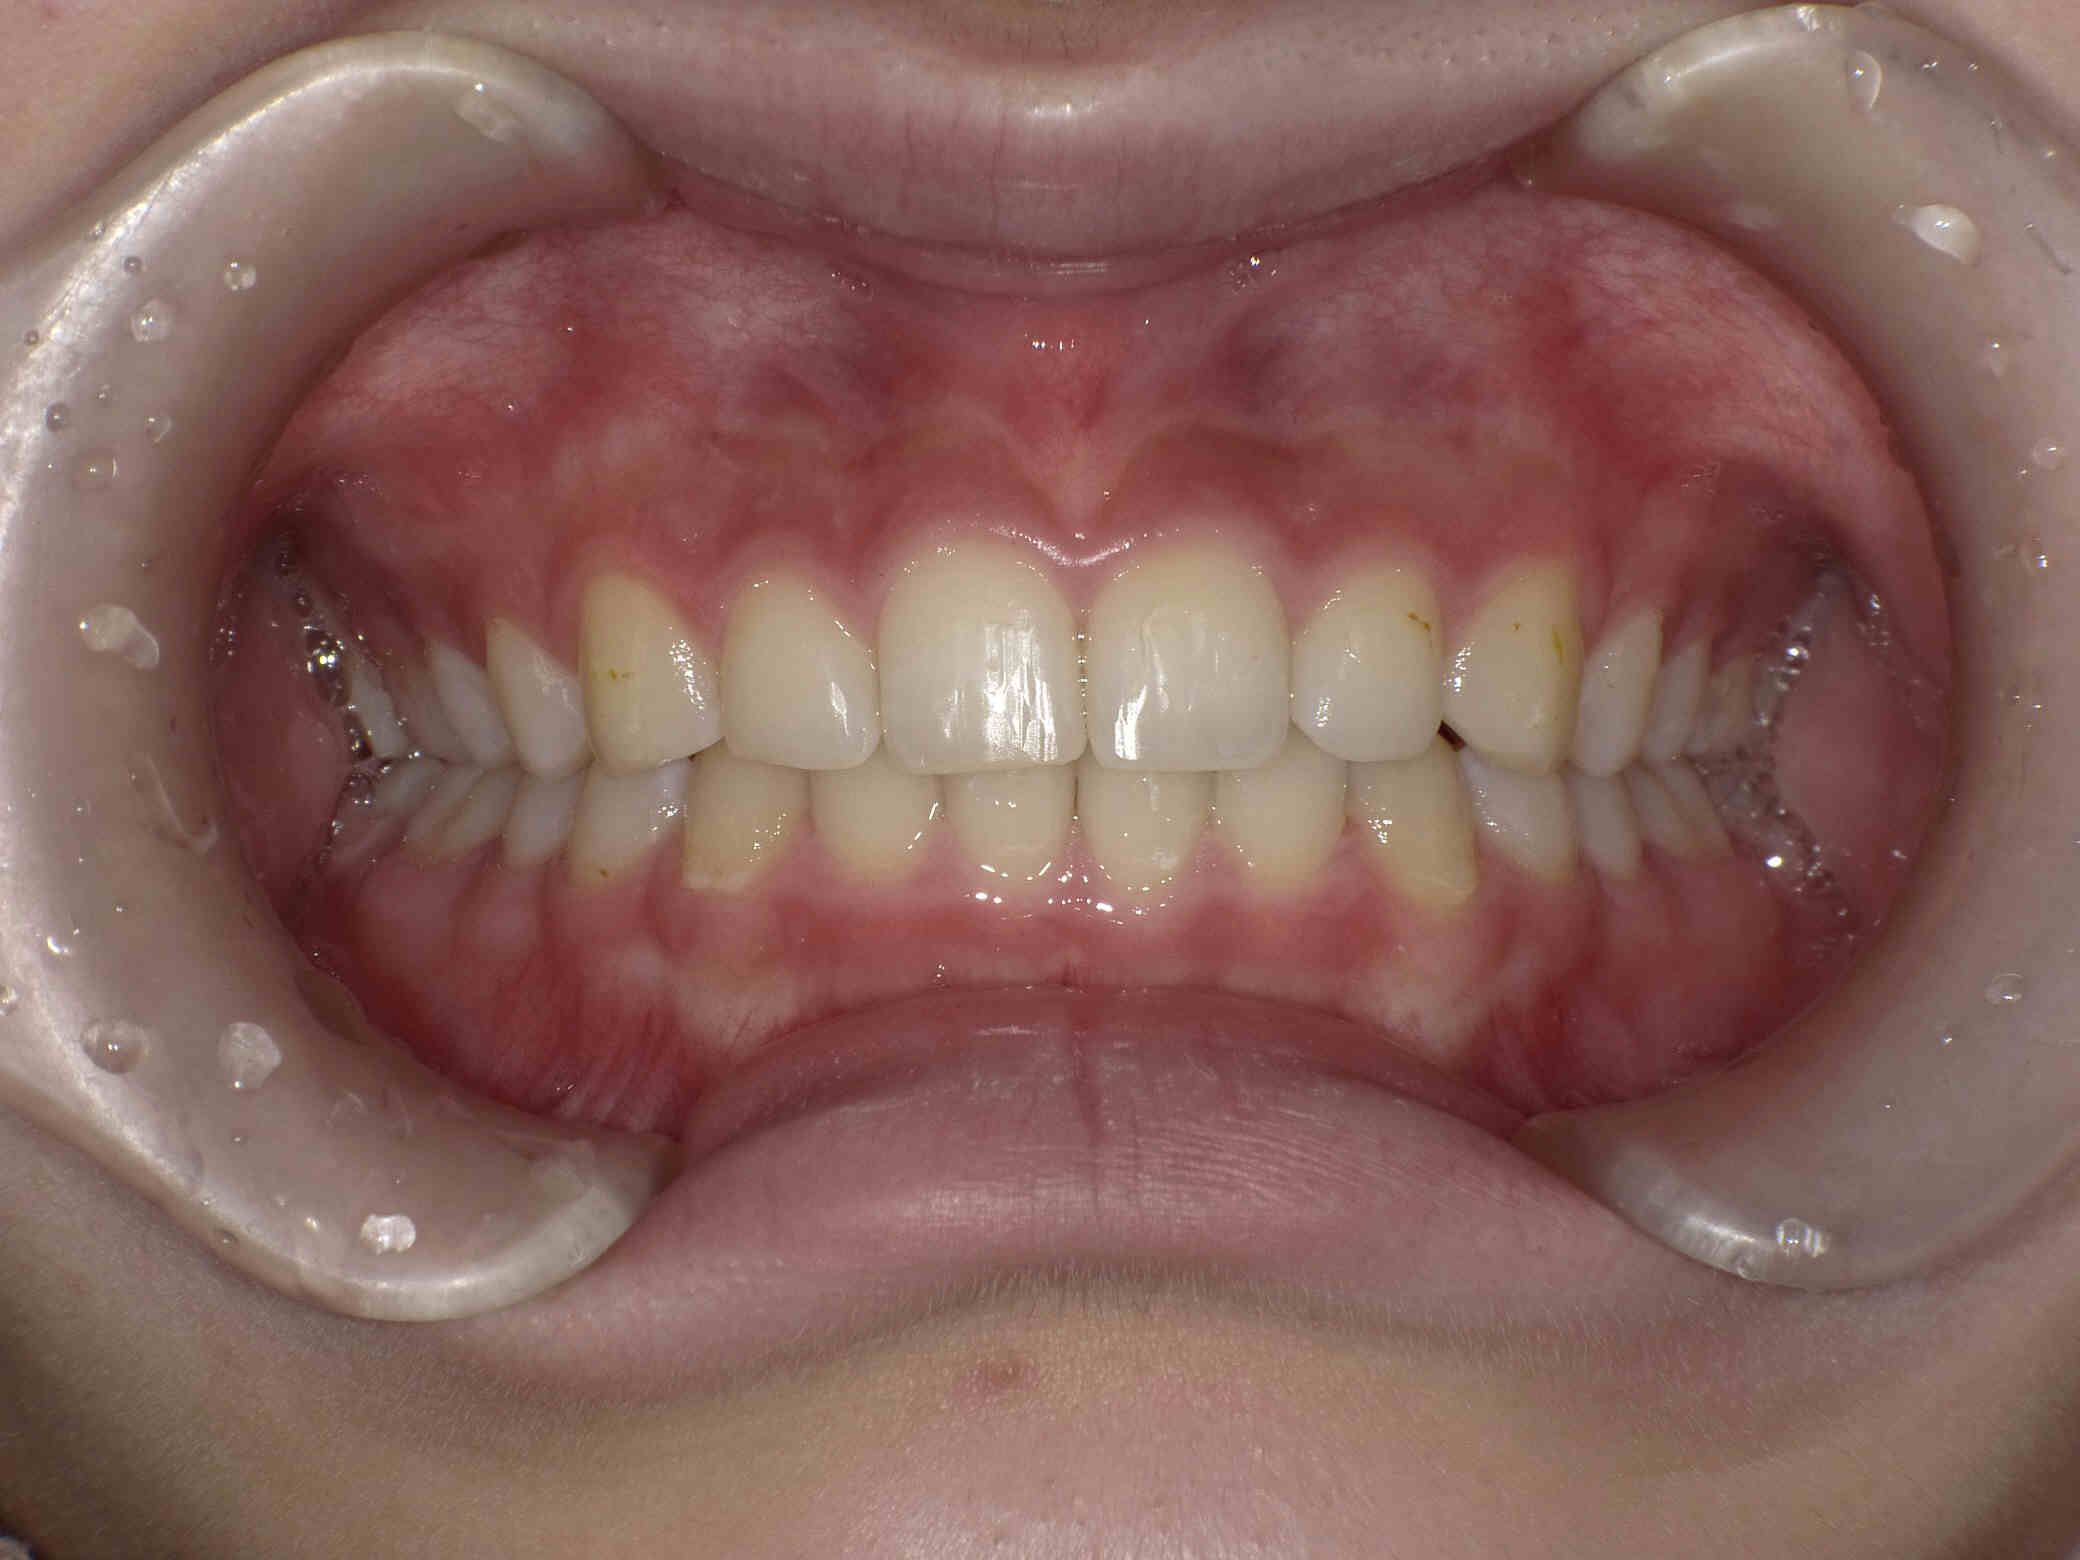

• 治療前

治療後

12歳6ヶ月〜スタートです。

やや出っ歯傾向で、噛み合わせが深く

歯並びがデコボコな鋏上咬合(はさみじょうこうごう)という状況でした。

上下の歯がすれ違っている状態で、一部の歯に過度の負担がかかってしまいます。

今回はご希望のワイヤー矯正で治療を行い、スタートから1年半で美しい歯並びに改善しました。